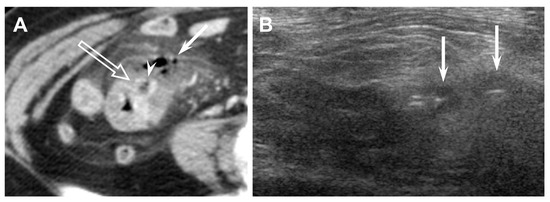

Figure 5. Seventy-year-old female (patient #7) with acute perforated ileal diverticulitis. (A) Axial CT scan shows terminal ileal wall thickening, an outpouching inflamed diverticulum (open arrow) with focal wall defect (arrowhead) at the mesenteric side of terminal ileum, extraluminal air with fluid (arrow), and mesenteric fat infiltration. (B) US scan with linear transducer also reveals extraluminal air bubbles (arrows) representing perforation.

The CT findings for acute ileal diverticulitis are summarized in Table 2. All 17 patients had ileal diverticulum along the mesenteric border. Inflamed diverticulum was seen in 16 patients (94.1%) (Figure 1). The remaining patient did not have an inflamed diverticulum at the center of ileal wall thickening with abscess; however, adjacent ileal diverticula supported the diagnosis of acute ileal diverticulitis with perforation, and barium study after 1 month demonstrated two ileal diverticula along the mesenteric border (Figure 2). Three patients had radiodense fecalith within the inflamed diverticulum (Figure 3). All 17 patients had mesenteric fat infiltration with varying degrees and ileal wall thickening. Five patients (29.4%) were diagnosed with perforated ileal diverticulitis, which had the following findings: abscess (n = 2) (Figure 2), extraluminal fluid with air (n = 3) (Figure 4), and/or focal defect in the diverticular sac (n = 2) (Figure 5). Mesenteric venous gas (Figure 4) and mesenteric venous thrombosis were seen in two patients (11.8%), respectively.

The US findings for acute ileal diverticulitis are summarized in Table 3. All patients showed outpouching inflamed diverticular sac connecting to the ileum, peridiverticular inflamed fat presenting as hyperechoic fat around the diverticulum, and increased color flow to the diverticulum and surrounding inflamed fat on CDI (Figure 1). The inflamed diverticulum exhibited variable echogenicity (Figure 2 and Figure 3). Like CT findings, eight patients had a single diverticulum and nine patients had multiple diverticula. Unlike CT, US examinations diagnosed perforated ileal diverticulitis in seven patients. The findings indicated that five patients had both abscess and extraluminal air bubble (Figure 4 and Figure 5), one patient had only extraluminal air bubble (Figure 6), and one patient had only abscess.